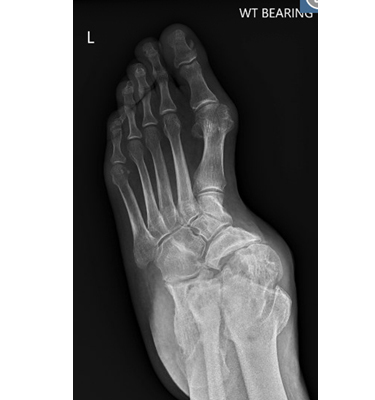

The ankle joint connects the leg to the foot and comprises three bones: the tibia, fibula, and talus. The tibia (shinbone) and fibula (calf bone) are the bones of the lower leg that articulate with the talus (ankle bone), enabling up-and-down movement of the foot. The joint surfaces of all these bones are lined by a thin, tough, flexible, and slippery surface called the articular cartilage, which acts as a shock absorber to cushion and reduce friction between the bones. The cartilage is lubricated by synovial fluid, which further enables smooth movement of the bones. Ligaments are tough, rope-like bands that connect bones to other bones, holding them in place to provide joint stability.

Ankle fusion surgery may be performed as an open surgery, where a large incision is made, or as a minimally invasive arthroscopic surgery, where small incisions are made to insert an arthroscope (a thin tube with a camera and light source) and miniature surgical tools. Open surgery is the commonly employed approach and involves the following steps:

- The joints are then fused together with the help of screws, wires, plates, or rods.